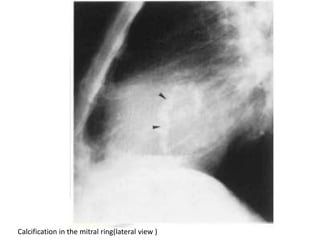

Calcification in the mitral ring(lateral view )

Calcification in themitral ring(lateral view )